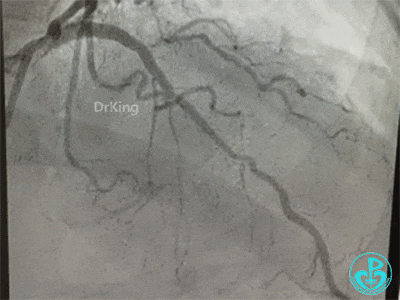

冠脉造影

右冠脉近中段不规则狭窄。短左主干中度狭窄,前降支开口严重狭窄,多功能造影导管推注造影剂时无反流,导管退出左主干开口造影发现左主干狭窄严重。

患者术中血压偏低,一度出现烦躁。及时IABP置入是手术能顺利完成的保障。术前的准备很全面,造影结果如下。